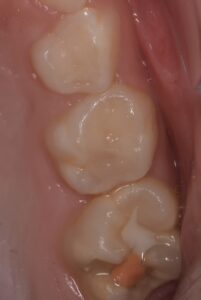

Pour les secteurs postérieurs, en fonction du délabrement tissulaire (PEB ou consécutif à une atteinte carieuse), on optera pour des restaurations directes en composite (Figures 11-12).

formation dentaire pédodontie Figure 11.

formation dentaire pédodontie Figure 12.

Figures 11-12 : Taitement postérieur par résine composite.